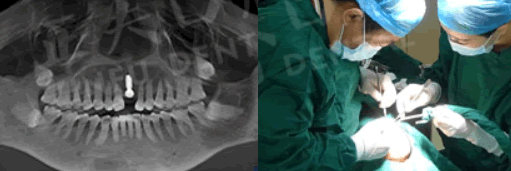

種植牙過(guò)程圖:

在種植過(guò)程中,李大媽幾乎沒(méi)有感覺(jué)到什么疼痛。